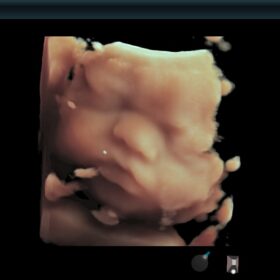

Ultrasound ARIETTA 850 SE – Image Gallery and Videos

Obstetrics 2D, Color and 4D mode